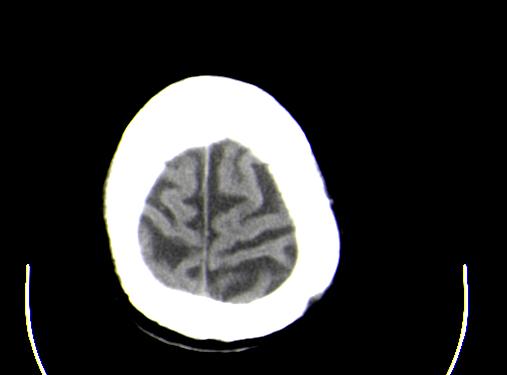

患者男性,67岁,头晕摔倒后来医院就诊,患者诉平时体健,否认有颅内病变史

脑萎缩;

2、脑萎缩。